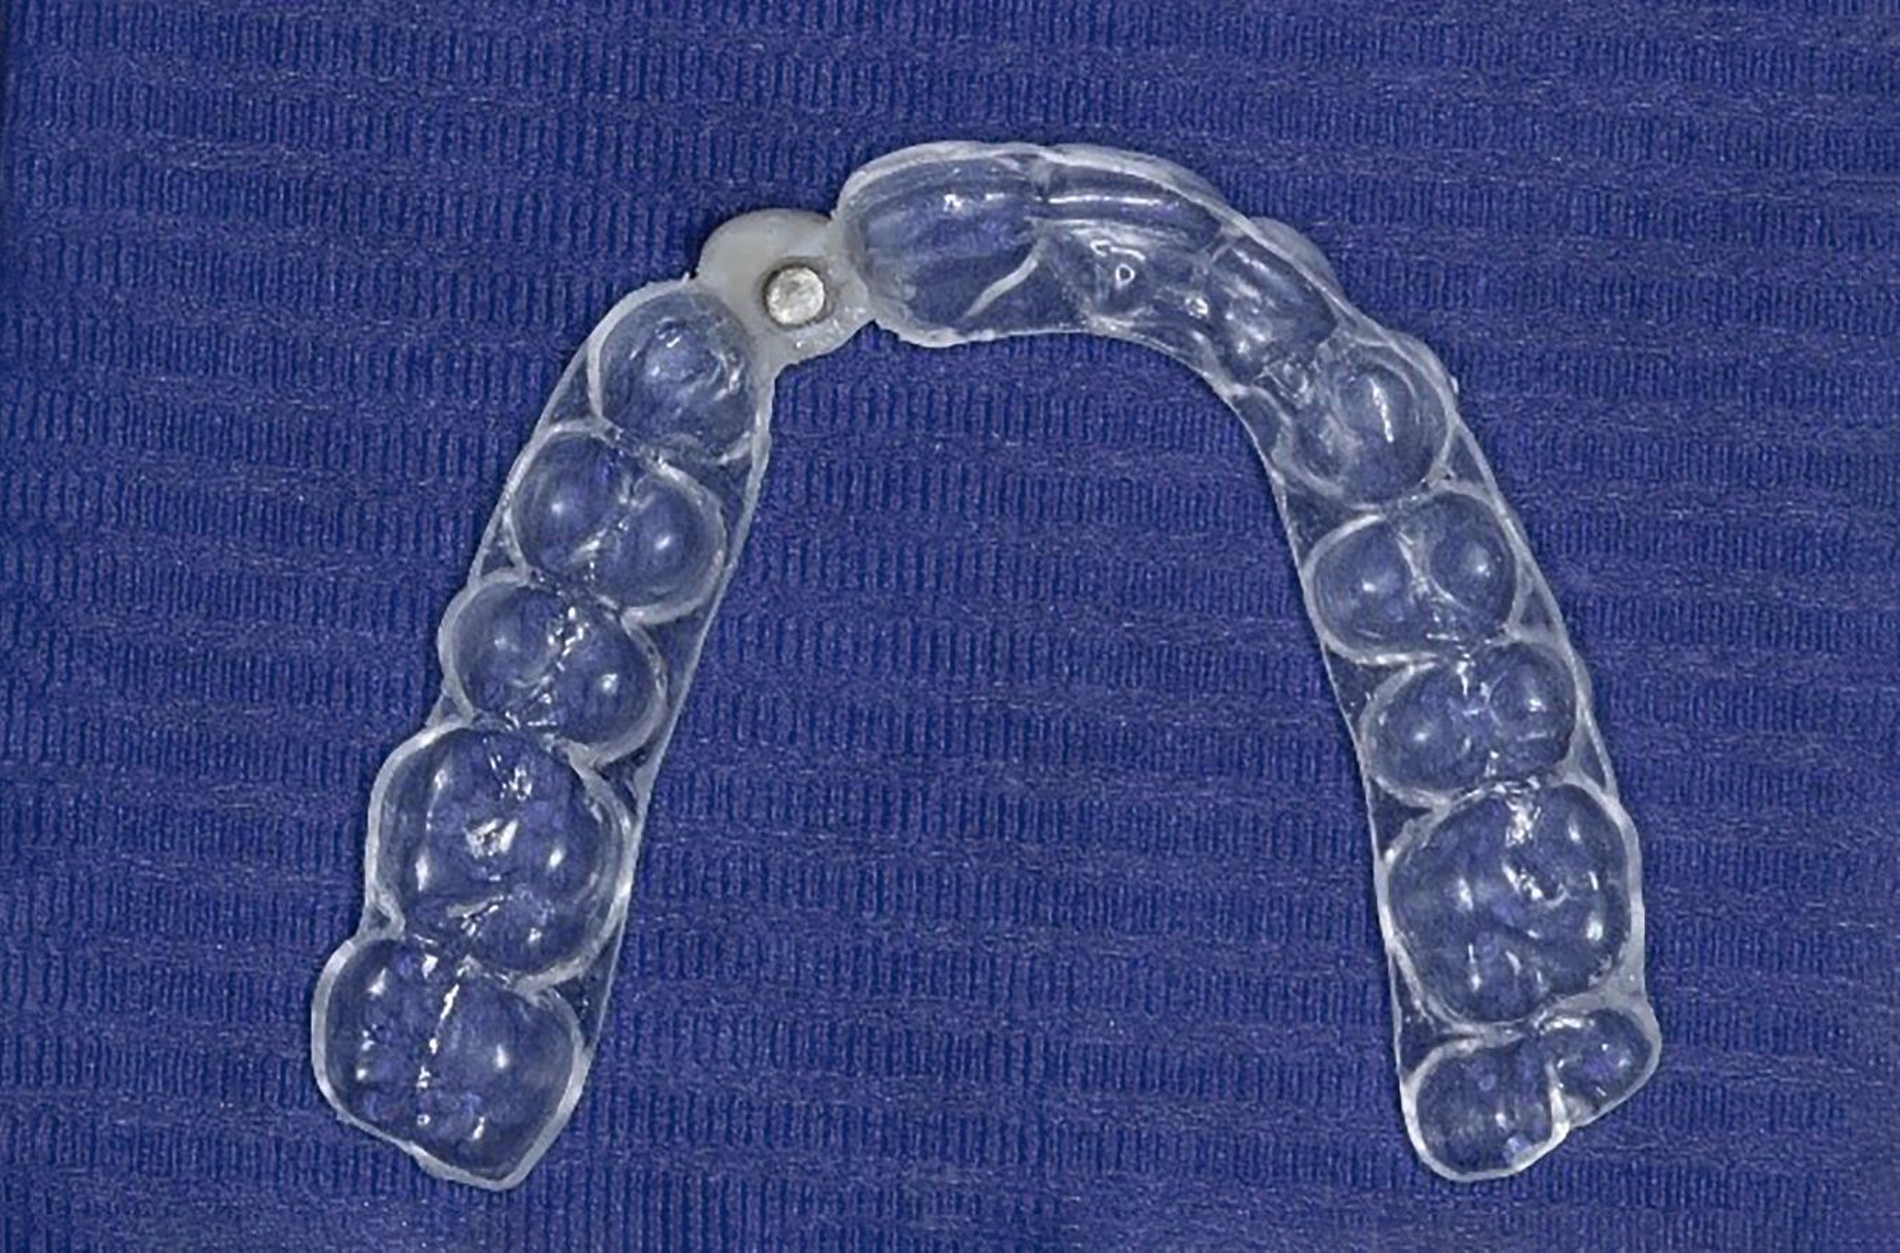

In Fall 2 wurde die Extrusion mit einem Magneten durchgeführt. Hier wird mittels Säure-Ätz-Technik ein Magnet mit 3 mm Durchmesser auf den verbliebenen Wurzelrest geklebt. Der Gegenmagnet wurde im Abstand von circa 2 mm in eine Tiefziehschiene einpolymerisiert. Dadurch war der Patient gleichzeitig für die Extrusionszeit provisorisch versorgt. Hilfreich ist hier ein im Vorfeld angefertigter, wenig resilienter Platzhalter. Des Weiteren hat dieses Vorgehen den Vorteil, dass die axiale Ausrichtung bereits optimal angepasst werden kann. Nach Bedarf sollten der Magnet weiter nach inzisal versetzt und eine Fibrotomie durchgeführt werden, bis der Wurzelrest ausreichend extrudiert ist.